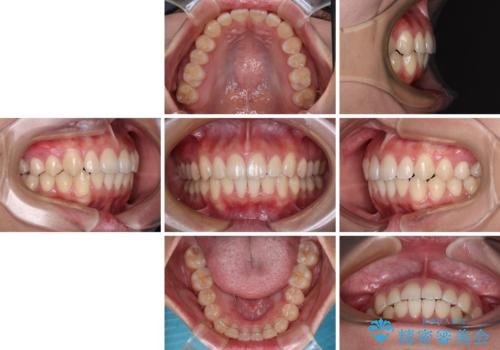

デコボコをワイヤー装置で改善 短期間で綺麗な仕上がりに

- デコボコを気にして来院された患者様です。

インビザラインでもワイヤー装置でも対応可能でしたが、自己管理の煩わしさの観点から、楽して治療のできるワイヤー装置を選択されました。

抜歯するほどではないものの、やや口元の突出感が気になっていたので、補助装置により上顎臼歯を後方に移動させることで、突出感改善を図ることとしました。

1年弱の短期間で、望み通りのスッキリとした口元に仕上げることができました。